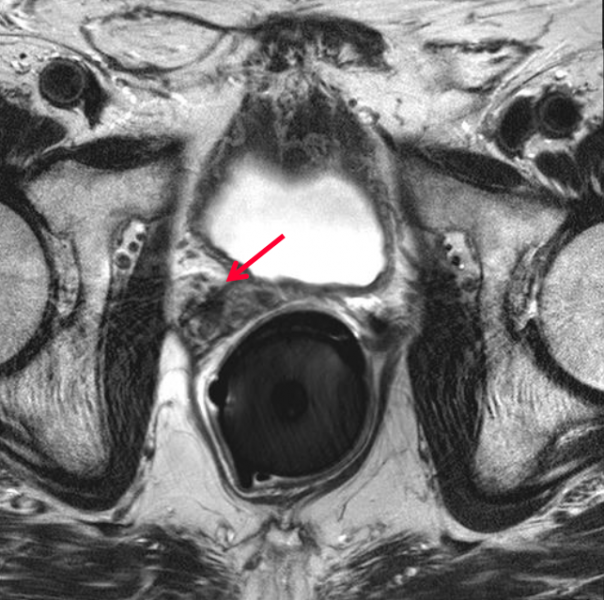

Regardless of the type of radiotherapy delivered, prostate cancer treatment requires high doses of radiation to achieve disease control. One important consideration during dose calculation is the position of the rectum, a portion of which often remains in the target treatment area. One strategy that has been employed in the past to protect the rectum and other radiosensitive areas is to create physical separation between the prostate and the rectum through use of a spacer. Multiple products and materials have been used in this capacity, the most recent of which is a hydrogel-based product that dissolves following treatment completion.

Massachusetts-based company Augmenix received U.S. Food and Drug Administration (FDA) clearance for the SpaceOAR System in early 2015. The hydrogel is administered as a liquid and solidifies into a soft gel that temporarily positions the anterior rectal wall away from the prostate. Following the treatment, the gel liquefies and is absorbed and excreted from the body in the patient’s urine.